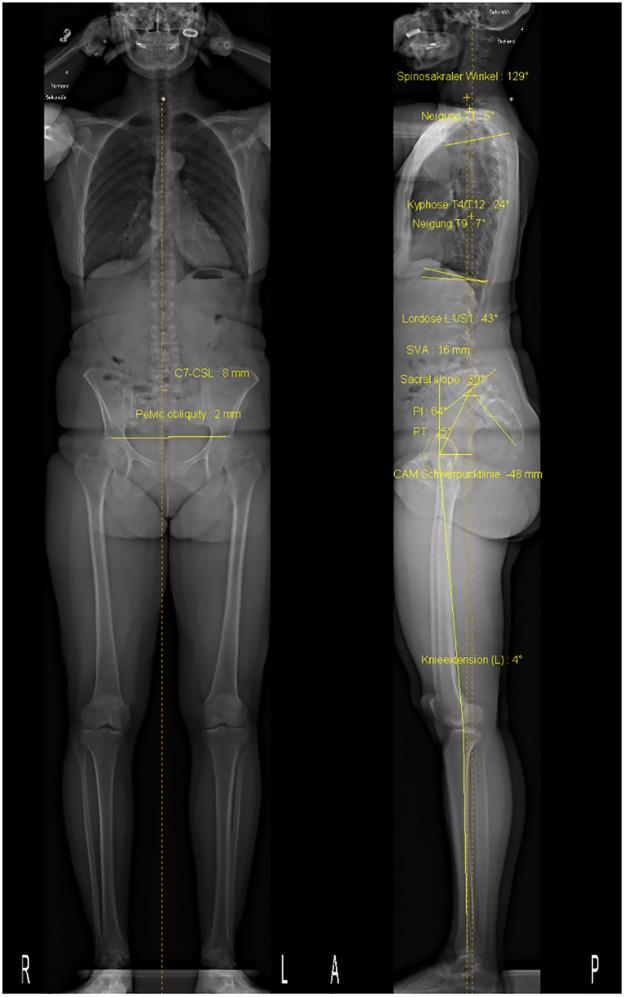

At baseline and 1-year follow-up, 122 patients with sLSS will be assessed clinically, perform the back-performance scale assessment and complete several patient-reported outcome measure (PROMs) questionnaires regarding overall health, disease-related symptoms and kinesiophobia. Posture and biomechanical parameters (joint kinematics, kinetics, surface electromyography, back curvature) will be recorded using an optoelectronic system and retroreflective markers during different tasks including overground walking and movement assessments before and after a modified Biering-Sørensen test, used to elicit paraspinal muscle fatigue. Measurements of muscle size and quality and the severity of spinal stenosis will be obtained using magnetic resonance imaging (MRI) and sagittal postural alignment data from EOS radiographies. After each study visit, physical activity level will be assessed during 9 days using a wrist-worn activity monitor. In addition, physical activity level and PROMs will be assessed remotely at 6-month follow-up.

在基线和 1 年随访时,将对 122 名 sLSS 患者进行临床评估、进行腰背表现量表评估,并完成多项与整体健康、疾病相关症状和运动恐惧相关的患者报告结局(PROM)问卷。使用光电系统和反射标记,在不同任务中记录姿势和生物力学参数(关节运动学、动力学、表面肌电图、背部曲率),包括在改良 Biering-Sørensen 试验前后进行的地面行走和运动评估,该试验用于诱发腰背肌肉疲劳。使用磁共振成像(MRI)和 EOS 射线照相的矢状位姿势数据测量肌肉大小和质量以及脊柱狭窄的严重程度。每次研究访问后,使用腕戴活动监测器在 9 天内评估体力活动水平。此外,在 6 个月随访时还将远程评估体力活动水平和 PROM。